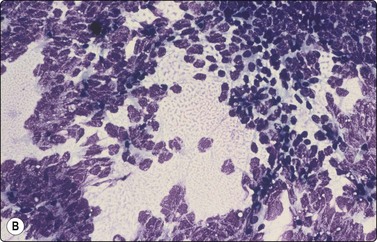

Yolk sac tumor (Figs 13.37 and 13.38)14,53-56,59-61,63

Most cytologic reports are based on FNA performed on metastatic sites. A detailed account of the morphologic spectrum of endodermal sinus tumor has been reported by Akhtar et al.53

image image

Fig. 13.37 Endodermal sinus tumor

(A) Polypoid epithelial fragment of large malignant cells with pale, almost clear, vacuolated cytoplasm (MGG, HP); (B) Corresponding tissue section (H&E, IP).

Fig. 13.38 Endodermal sinus tumor

(A) A glomeruloid cell cluster with vacuolated cytoplasm on a mucoid background (DQ, IP); (B) Cell cluster with a vascular stalk and several hyaline globules.

Criteria for diagnosis

Mucoid background,

Glomeruloid structures,

Schiller-Duval bodies (characteristic finding when present),

Very immature cells, prominent nucleolus, basophilic cytoplasm,

Small naked nuclei,

Intra- or extracellular PAS-positive hyaline globules (AFP positive),

Prominent cytoplasmic vacuoles and distinct cell boundaries confer a clear-cell appearance,

Immunocytochemistry: focal staining for AFP, AE1/AE3 and PLAP; negative for OCT image.

Pure yolk sac tumors are almost always encountered in infants and young children but rare in the first 6 months of life.49 In adults, this pattern is seen in approximately 40% of nonseminomatous GCT;12 however, it can easily be mistaken for embryonal carcinoma in FNA smears. This is why most reported cases are of metastatic tumors. Hyaline globules and eosinophilic membrane-like material are hints to the diagnosis of this tumor type (Fig. 13.38B). In infants and young children, the aforementioned cytological criteria permit a confident diagnosis by FNA.